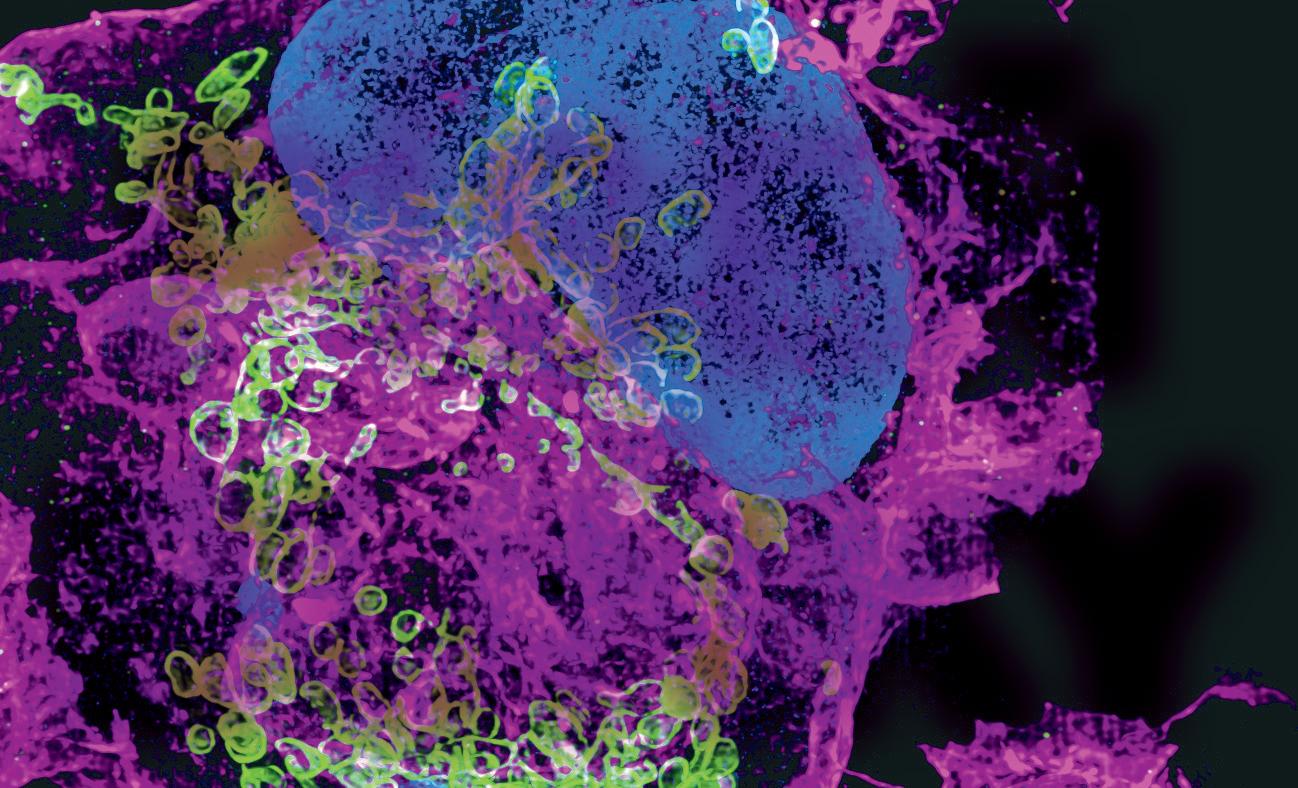

Fotografie na obálce: „Cellular harmony: The Interplay of action, mitochondria and the nucleus in B cells“. Vítězný mikrosnímek soutěže CELLIM Best Microscopy, Picture Contest 2024, autorem je Narenda Varma Gottumukkala, Masarykova univerzita, CEITEC, výzkumná skupina Michala Šmídy.